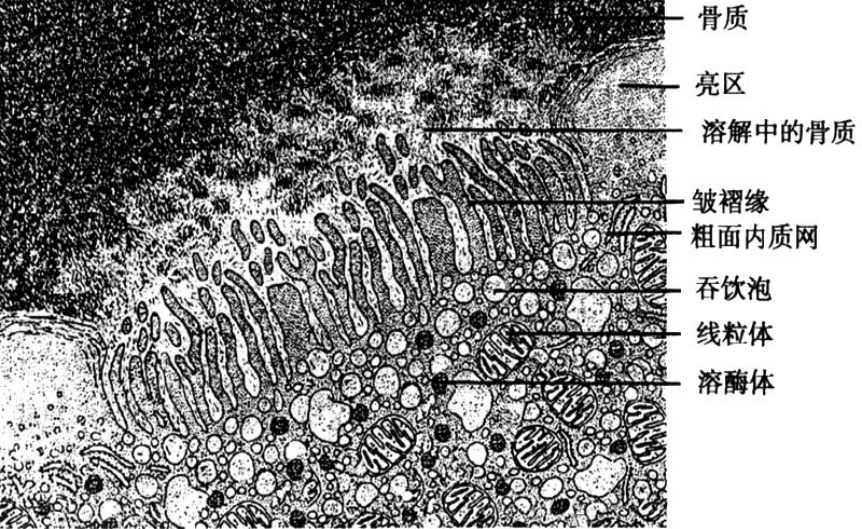

4.破骨细胞

●形态:

光镜结构:多个单核细胞融合而成,体积大,6-50个核;胞质嗜酸性;贴骨侧有皱褶缘。

超微结构:溶酶体和线粒体发达;皱褶缘侧多突起,皱褶缘深面有许多吞噬泡。

●分布:骨组织边缘。

●功能:释放多种水解酶和有机酸,溶解骨质;吞噬分解的骨质成分。

破骨细胞超微结构模式图: